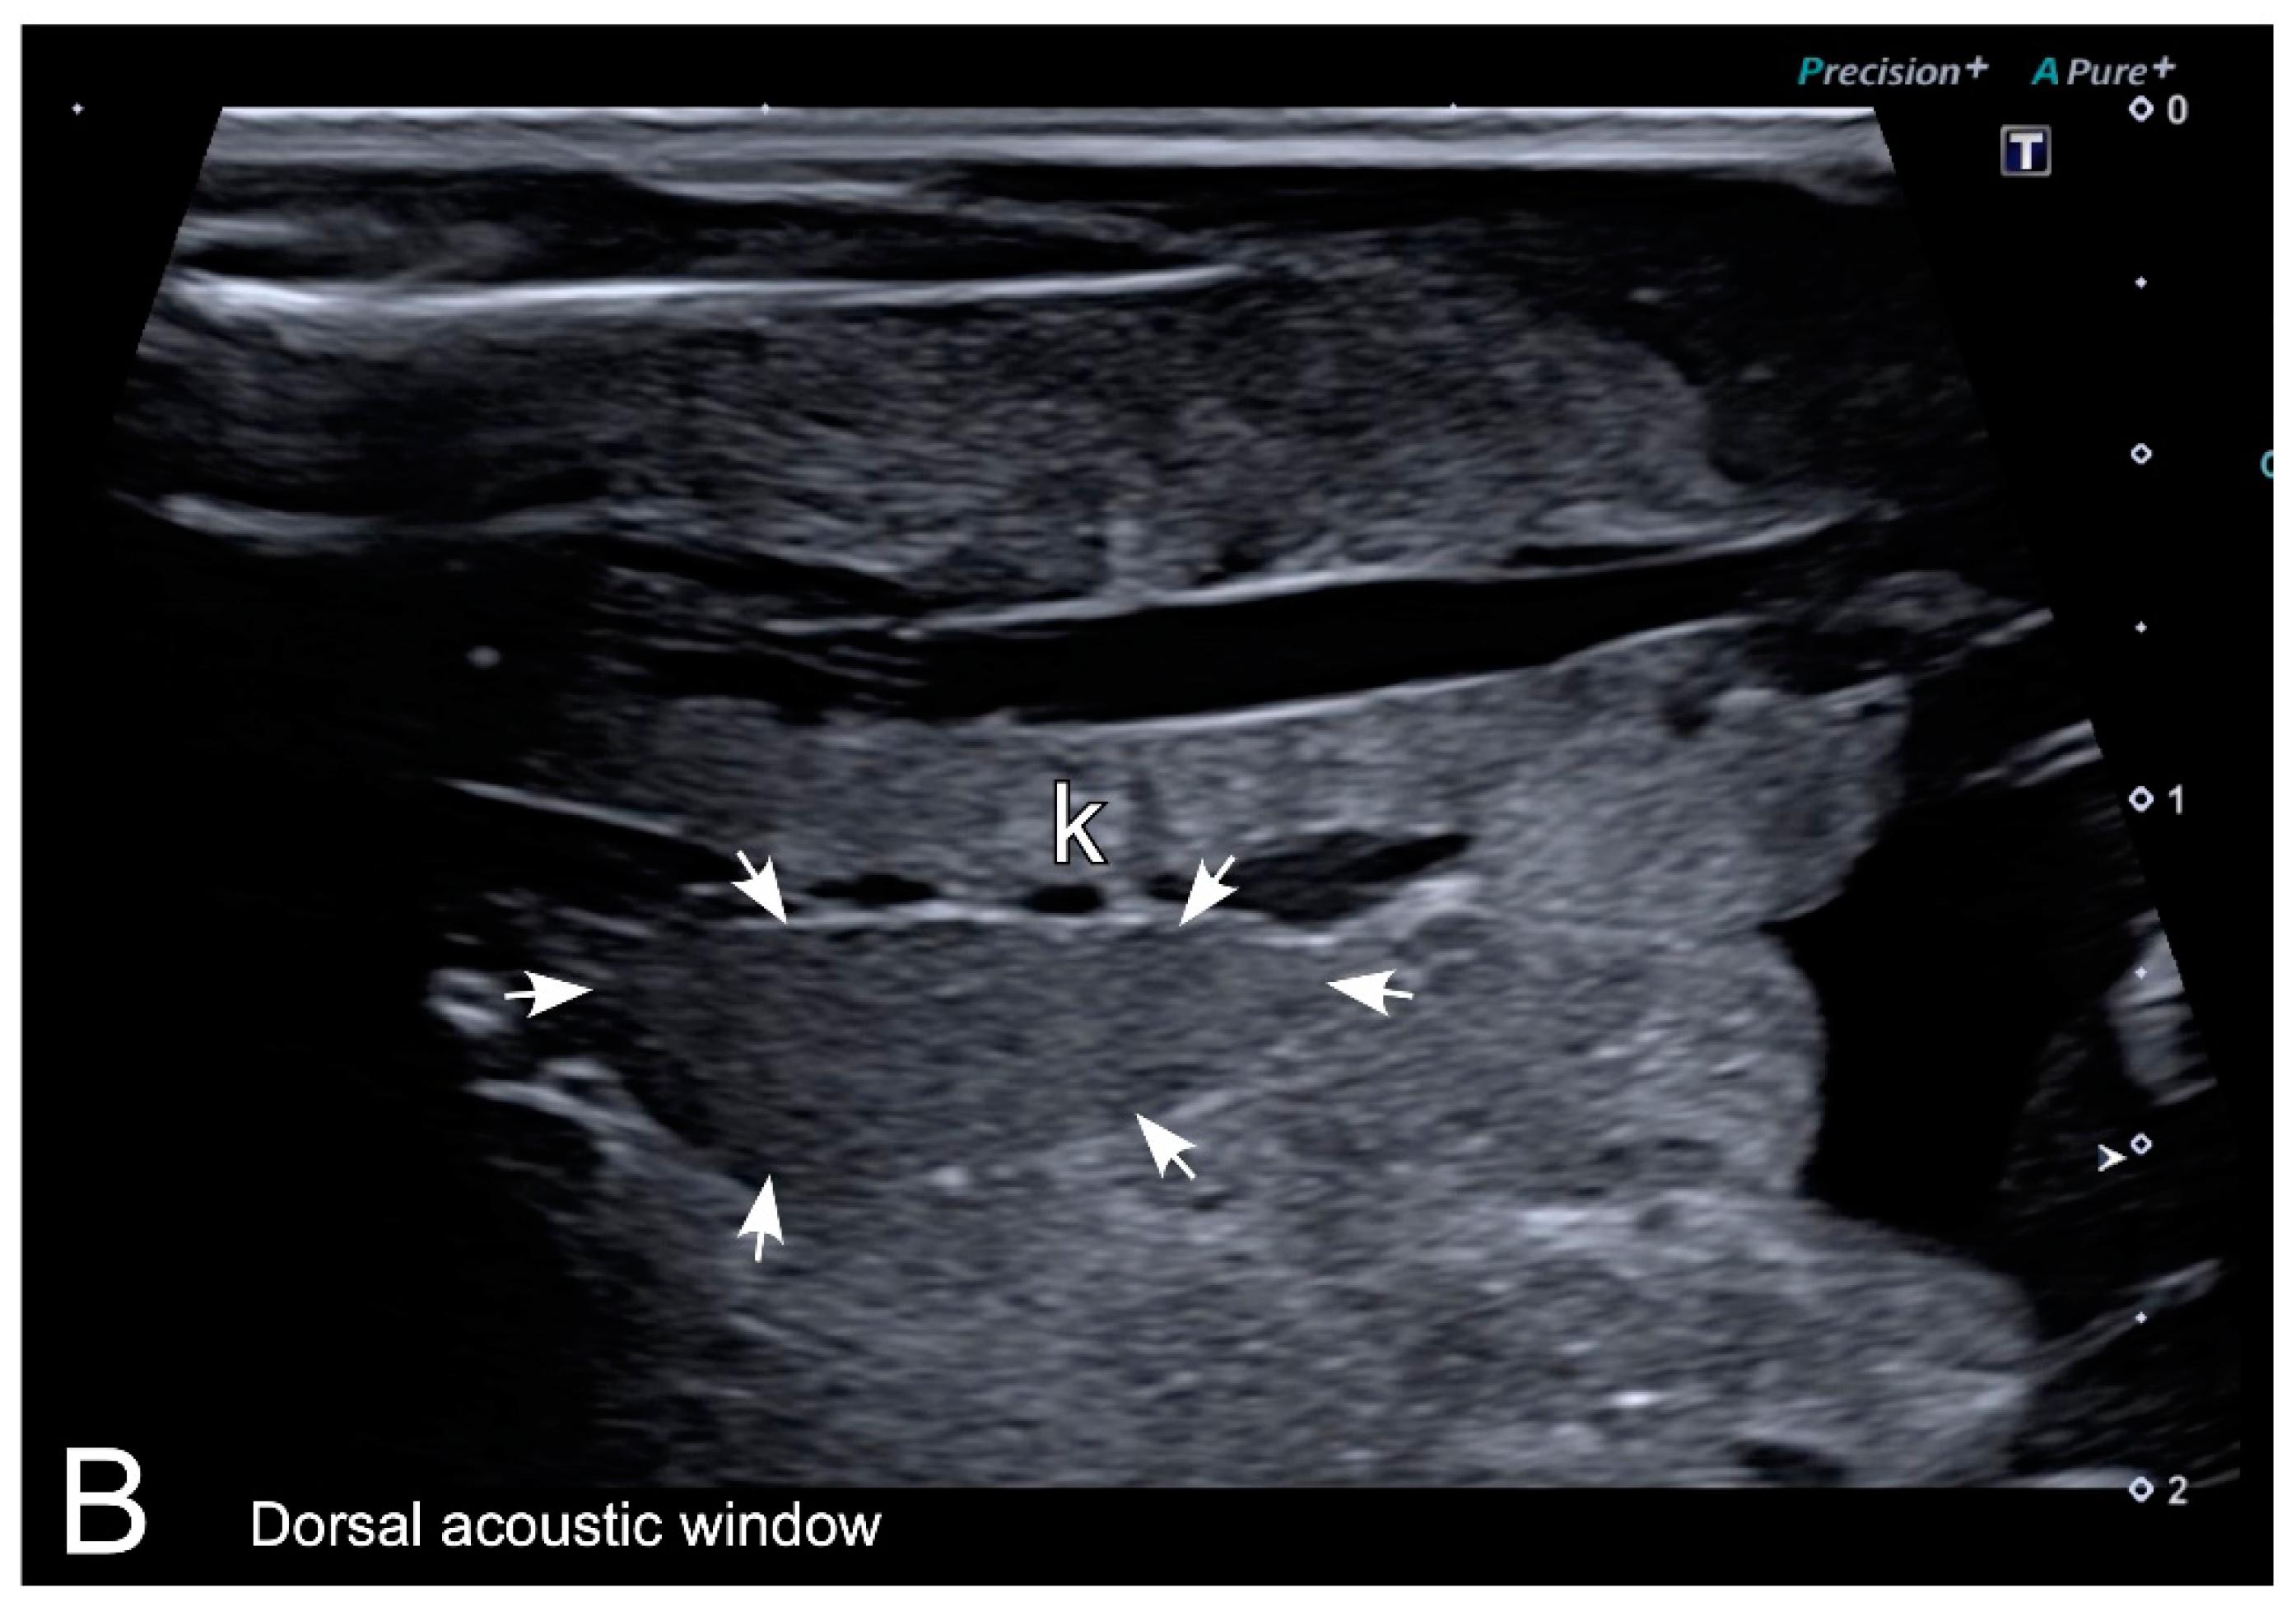

Figure 7. Representative HR-US images of Kaloula pulchra (A) and Xenopus laevis (B) males obtained in the longitudinal plane using a dorsal acoustic window. The testes (delimited by arrows) appeared as structures with oval morphology, mid echogenicity and homogenous echotexture. Testes were located just ventral or ventrolateral of the ipsilateral kidney (k). |